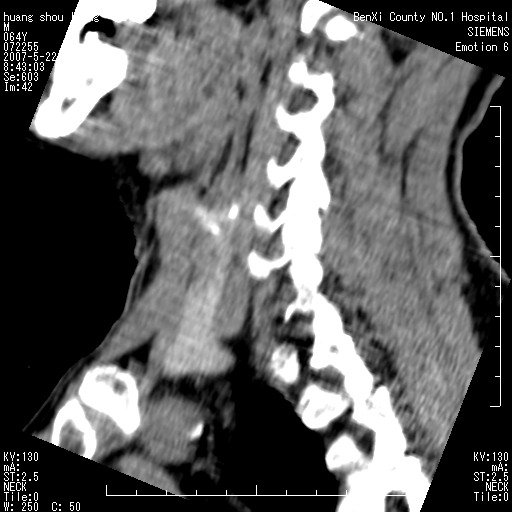

标题: CT8337:颈部包块8年,颈部CT和VRT,请讨论。

男性,64岁。颈部包块8年。最近增大。

对不起大家,可能是片子发太多有点乱,正常腮腺在下颌角的外侧,颌下腺在下颌体的中部内侧,本例在下颌角内侧偏下,和腺体一点关系都没有,从vrt和mpr上可以很明显看出来,再者肿块是好多粘连在一块的,大家在仔细看看,左侧可能也是吧,我还是考虑为肿大的淋巴结融合在一块,但性质??????

右侧腮腺下部均匀软组织密度肿块,外形不规则,与周围组织分界清晰,考虑右侧腮腺混合瘤或多形性腺瘤。

大家好,病理结果出来了,如大家所说,颌下腺混合瘤。

唉,解剖没学好吧,我诊断错了,不过还是有些不理解回去我在多看看书,谢谢大家的参与,以后我还会奉献好的病例。